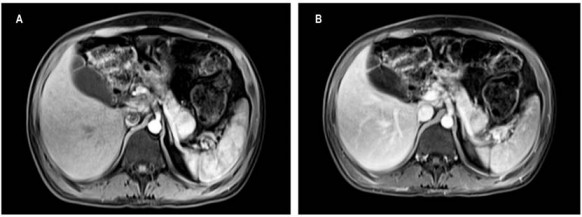

Para confirmar la impresión diagnóstica de vipoma, que ganó fuerza con la respuesta positiva a la prueba terapéutica con octreotida, se realizó una resonancia magnética nuclear (RMN) de abdomen con contraste, la cual mostró una masa sólida hipervascular de 22 mm en la cola del páncreas (Figura 1), sin lesiones metastásicas. La lesión era susceptible de manejo quirúrgico, por lo que el paciente fue dirigido a una pancreatectomía distal laparoscópica más esplenectomía, por el grupo de cirugía hepatobiliar.

En el caso de lesiones pequeñas, la RMN con gadolinio cuenta con la mayor sensibilidad (91 al 94%) 14; sin embargo, tanto la TC multifásica como la RMN permiten la planeación del abordaje quirúrgico y su seguimiento posterior 14,17.